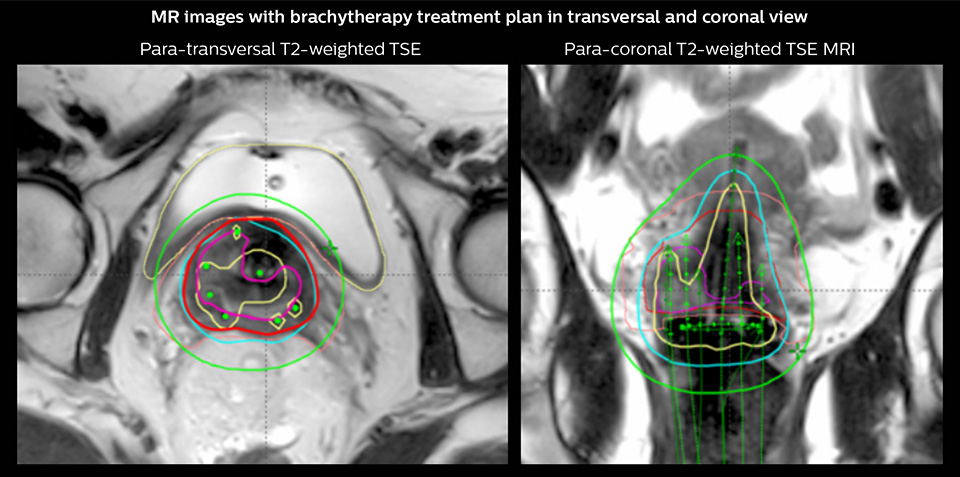

Brachytherapy

Two pulsed dose rate (PDR) brachytherapy fractions were delivered after end of EBRT in weeks 6 and 7.

One week prior to the first brachytherapy fraction, pre-planning was performed. Pre-planning involved insertion of intracavitary tandem-ring applicator and MR imaging with applicator in place.

An MRI-based pre-plan was carried out to determine the number, position and length of needles to be implanted through the ring applicator. Brachytherapy was delivered with the tandem ring applicator combined with 6 interstitial plastic needles.

Red CTVHR; Pink residual GTV; Yellow 200% isodose; Cyan 85 Gy EQD2 isodose; Green 60 Gy EQD2 isodose; Green applicators, needles

Brachytherapy dose calculation based on MRI

“On the treatment day we insert the brachytherapy applicator, which has channels that go into the uterus and in the upper vagina just below the cervix. We may have additional needles targeting the parametrial infiltration. At Aarhus we use an MR-compatible applicator based on a tandem-ring system with a cap with holes for guidance of interstitial plastic needles. We also use individualized 3D-printed applicators when needed. With the applicator in place we then perform another MRI exam. These images are used to help us identify the applicator, the organs and the target. And we use them to do the treatment planning,” says Dr. Tanderup.

“Both target and organ delineation as well as dose calculations can be based directly on the MR images. With external beam radiation therapy, dose calculations are based on x-ray attenuation derived from CT. However, brachytherapy dose calculation is performed in a simpler way and can be based directly on MRI without any problem.”

MRI sequences for target volume delineation and applicator reconstruction

“The target definition is based on T2-weighted images. We recommend planning the sequence orientation relative to the applicator, so we perform a para-transverse imaging series, and also para-sagittal and para-coronal sequences,” says Dr. Tanderup.